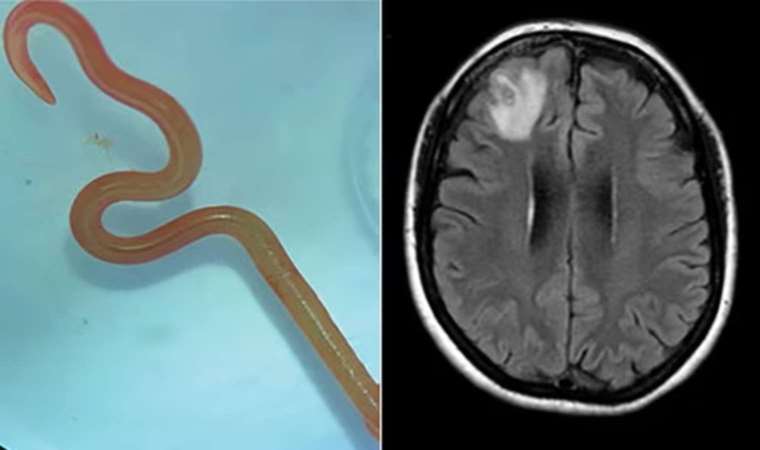

Dünyada bir ilk Dünyada bir ilk Unutkanlık ve depresyon şikayetleri görülen hastanın beyninden canlı solucan çıkarıldı.